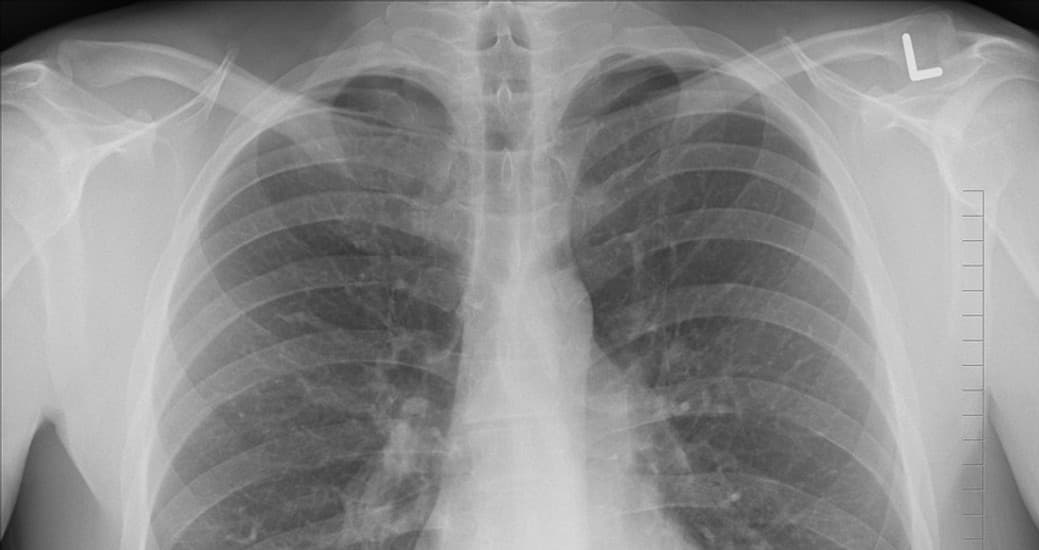

تقوم آلة التصوير بإطلاق الأشعة السينية على الهدف المصوّر، يتم امتصاصها بمعدلات مختلفة بواسطة العظام والأنسجة. تسمح الأنسجة الرخوة للأشعة بالمرور، بينما تمتص العظام الأشعة. باستخدام فيلم الأشعة السينية، يمكنك تطوير صورة بناءً على تفاوت نفوذية الأعضاء للأشعة السينية. بهذه الطريقة يمكنك رؤية مخطط عظامك.

ما الذي تحتاجه العيون لتتمكن من الرؤية بالأشعة السينية؟

ستحتاج العيون الخارقة إلى إطلاق أشعة سينية على الهدف، وبعد ذلك ربما يستطيع الدماغ تحليل أجزاء الأشعة السينية التي تم امتصاصها واختلاف النفوذية بين الأجسام. ستكون الرؤية متقطعة لأنّ هذه الآلية ستسمح له برؤية بعض المواد وليس غيرها. ربما سيحتاج المرء إلى القيام بالكثير من التجارب لمعرفة ما الذي لا يمتص الأشعة السينية كما سيتوجب عليه استخدامها بعناية للحد من إطلاق الأشعة السينية حتى لا يتعرض الناس للأشعة بشكلٍ مفرط فمن المعروف أنّ إشعاع الأشعة السينية ضار.